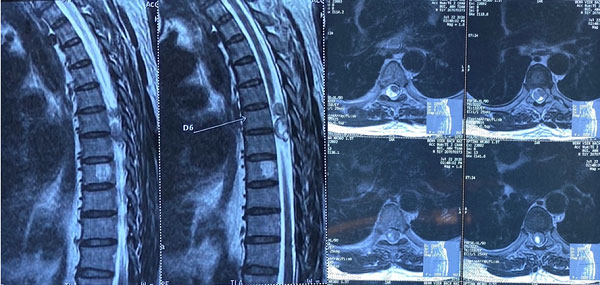

Cần khám và điều trị sớm các trường hợp U cột sống ngay khi có biểu hiện các triệu chứng trên. Các Bác sĩ sẽ thăm khám và chỉ định người bệnh chụp chiếu để chẩn đoán xác định bệnh như chụp X- quang, MRI, CT-Scanner…